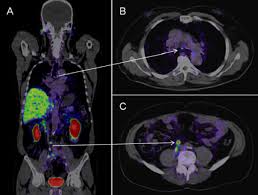

최첨단 현대의학으로 가장 적절한 방법이 양전자단층촬영술(Positron Emission Tomography, PET)이라고 나는 생각한다. PET는 체내 대사 변화를 촬영하는 기기로 CT나 MRI 다음에 개발된 영상장비이라고 한다.

요즘은 여기에 CT를 붙여서 PET 영상과 CT 영상을 융합해 서로 약점을 보완해 검사의 질을 더욱 높이고 있다고 한다.

여기에 방사성 핵종 F-18를 붙여(F-18 FDG라고 함) 혈관 주사하면 빨리 자리는 암세포는 포도당이 더 필요해 정상 세포보다 10∼100배 더 많이 모여들고 이를 방사능으로 촬영해 찾아낸다. 암이 1㎝만 돼도 10조개의 암세포가 있어 CT, MRI 소견이 애매한 경우 유용하게 쓰인다.

PET의 또 다른 장점으로 거의 모든 종류의 암을 찾아낼 수 있다는 것이라고 한다. 일반적으로 암세포는 포도당 대사가 높기 때문이라고 한다.

또 머리끝에서 발끝까지 촬영해 어느 곳에 있는 암이라도 잡아낸다. 다시 말하면 사각지대가 없다고나 할까? 이미 일본에서는 이 방법으로 암을 검진하는 프로젝트를 성황리에 진행하고 있다고 한다.